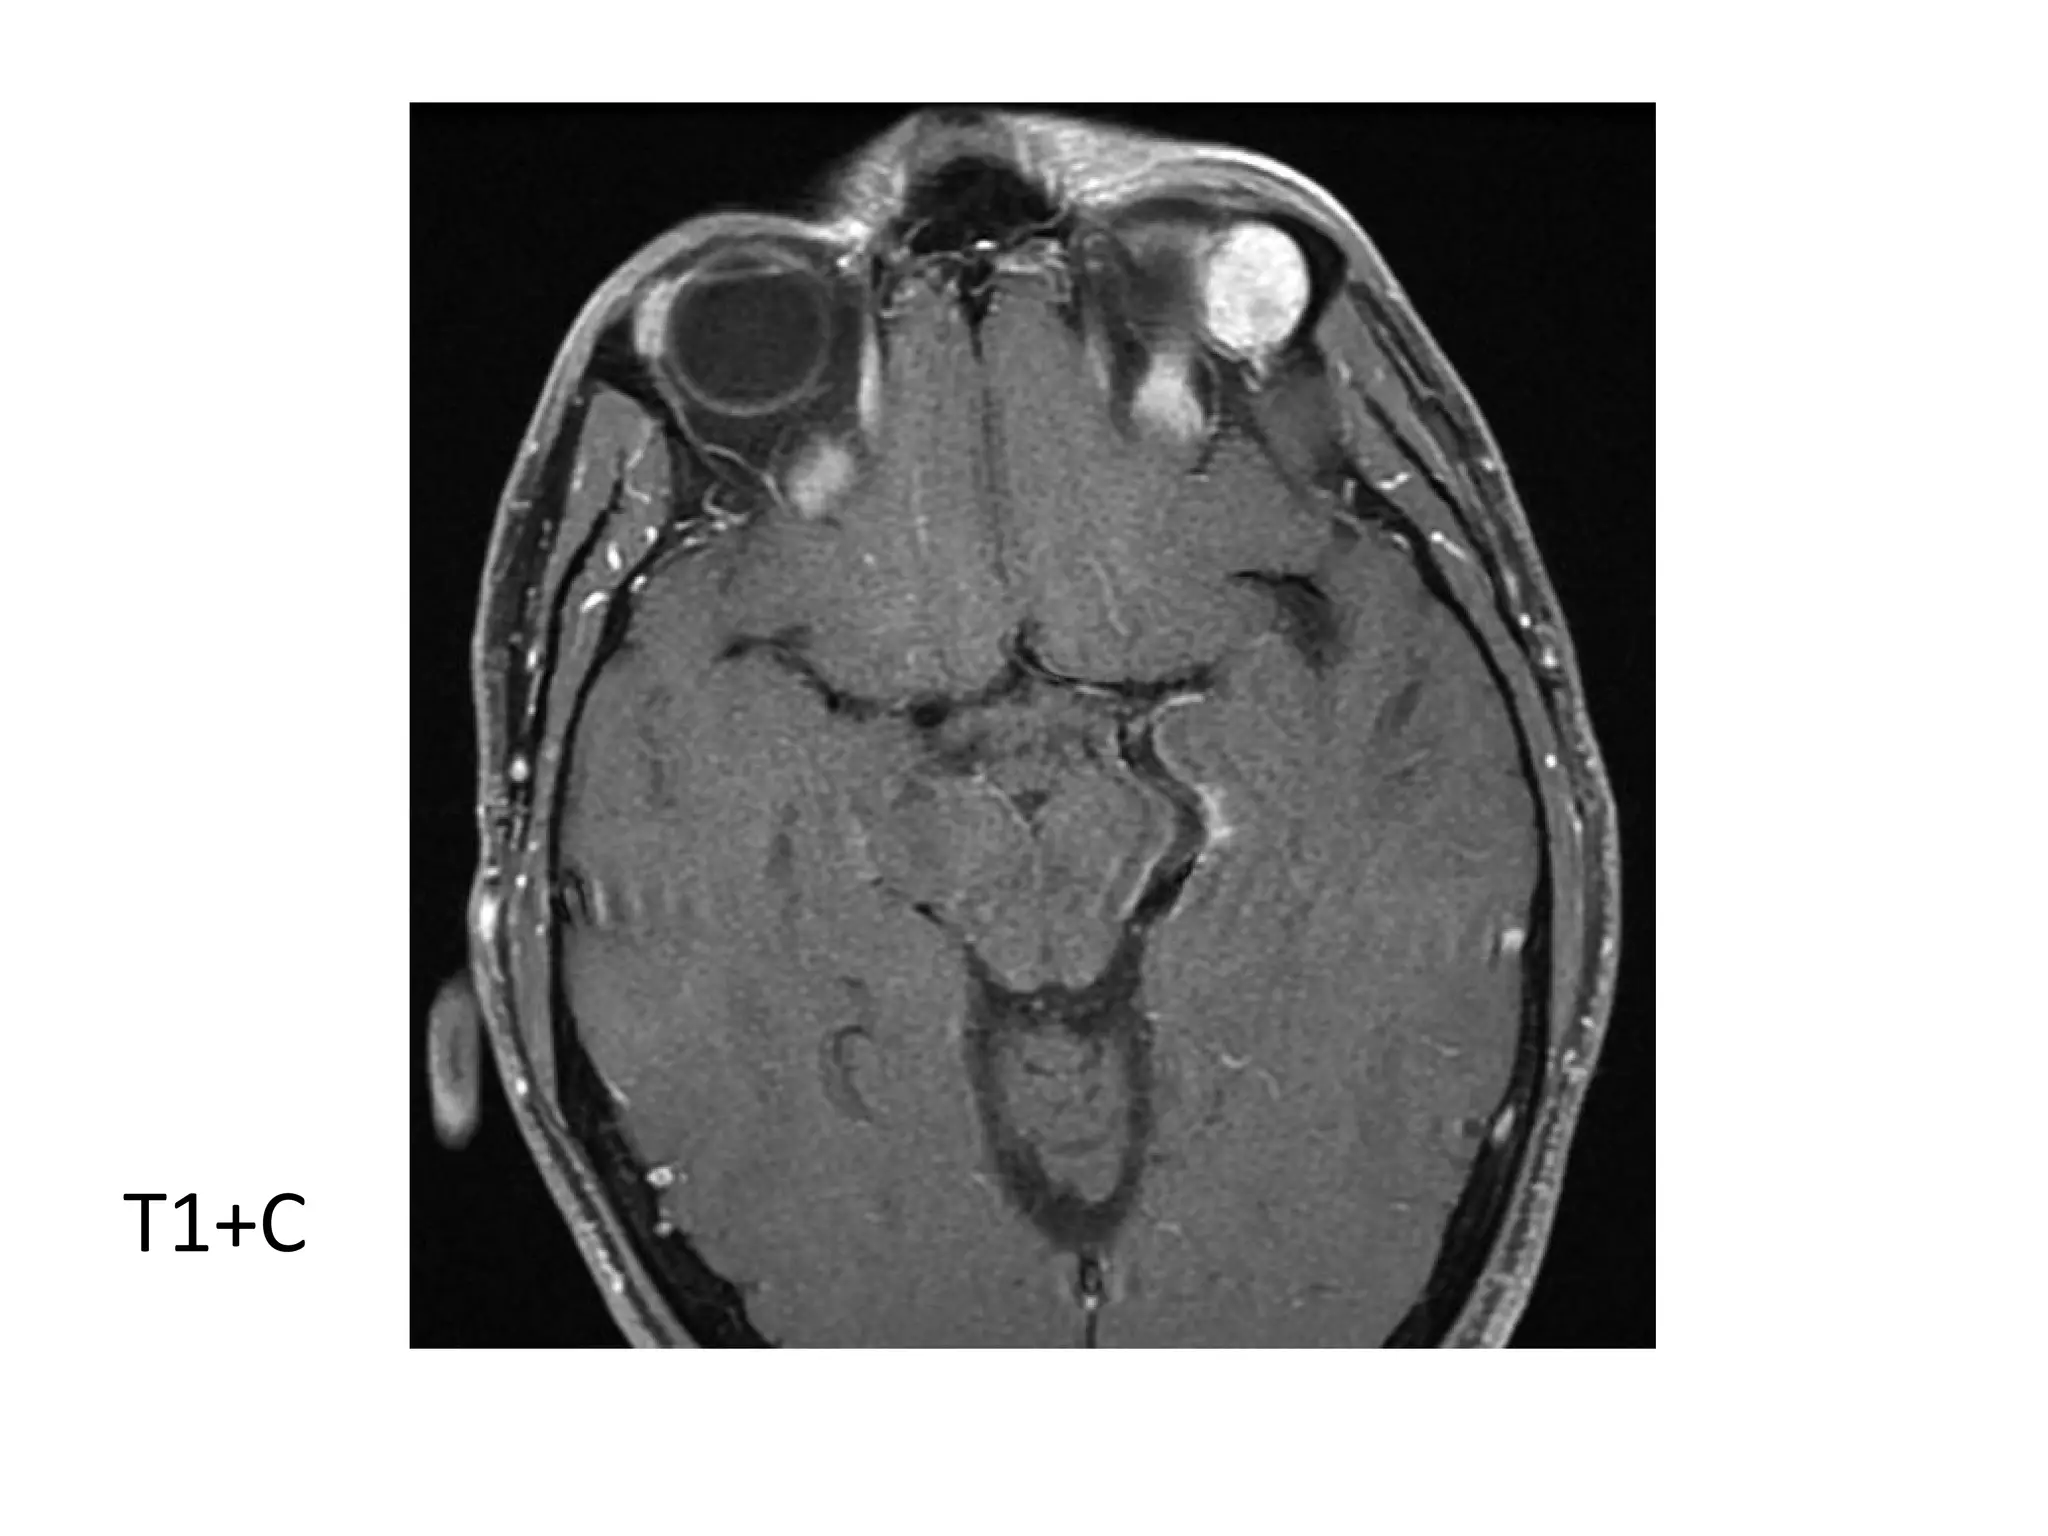

Optic nerve sheath meningioma in a 62-year-old patient who presented with blurry

vision of the right eye, axial T1+C fat-suppressed shows an avidly enhancing tumor

along both sides of the right optic nerve, the intraoptic and intracanalicular

portions of the optic nerve are involved (arrows), as well as the prechiasmatic

portion of the intracranial optic nerve (arrowhead). * = normal left intracranial

optic nerve